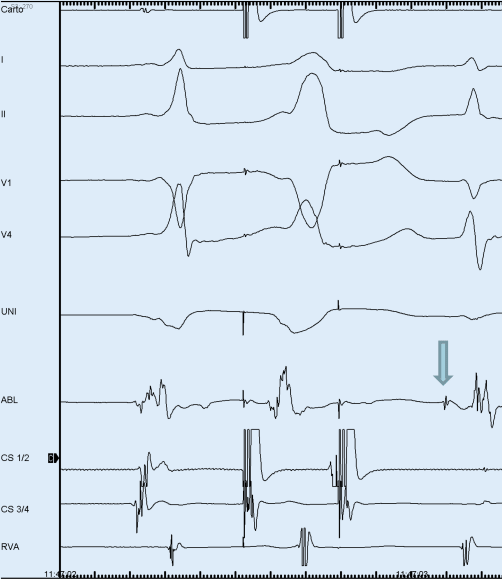

AV-Reentry-Tachykardie und Wolff-Parkinson-White-Syndrom | Herzschrittmachertherapie + Elektrophysiologie